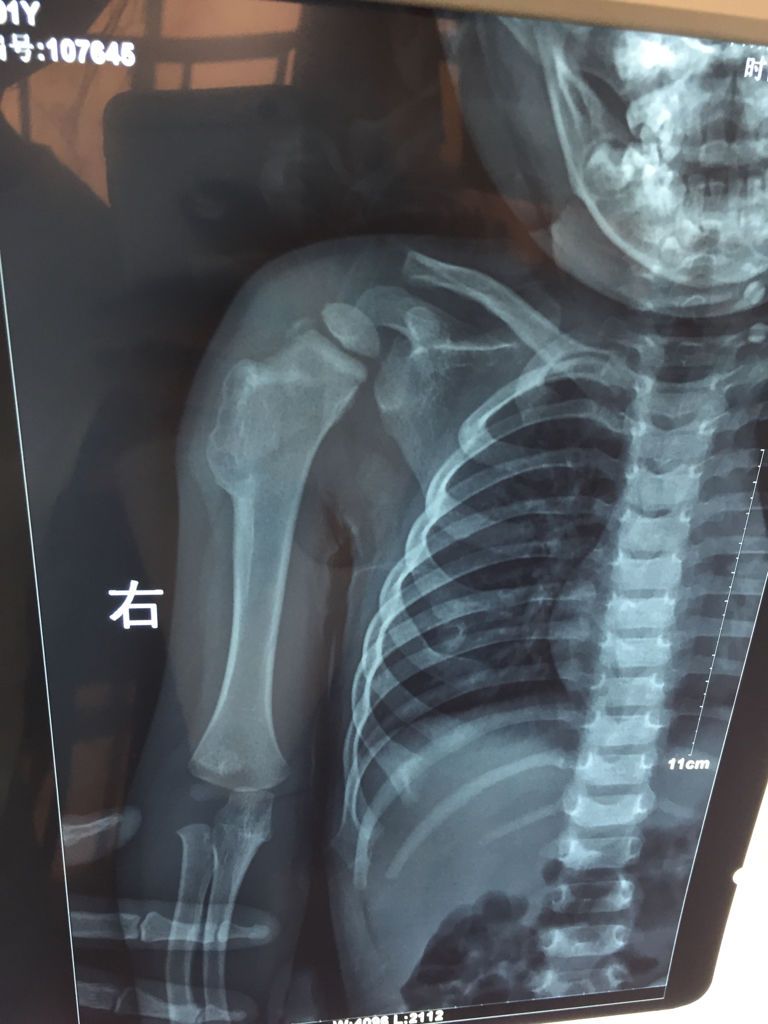

两岁宝宝胳膊有个骨肿瘤,偶然发现,拍了片子,没有任何症状

这种情况应该及时去骨科做检查治疗。